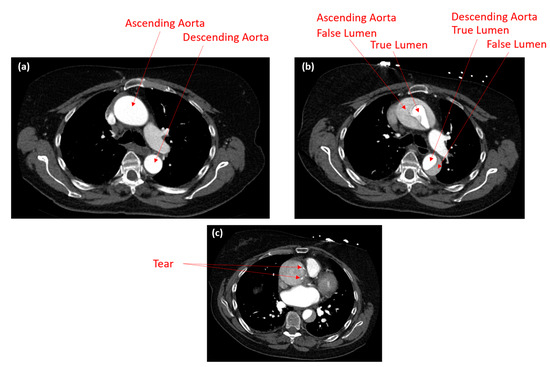

2.1. Patient-Specific CT Scans

2.2. 3D Geometry